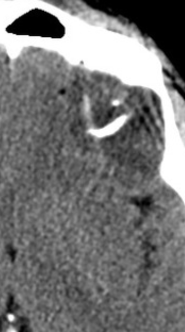

Oligodendrogliome (grade II)

- Comme un astrocytome diffus mais 1p19q co-déletion

- Calcifications ++

- Parfois kystes

cerebrales cerebrale tumeur oligo dendro dendrogilome oligodendrogliome